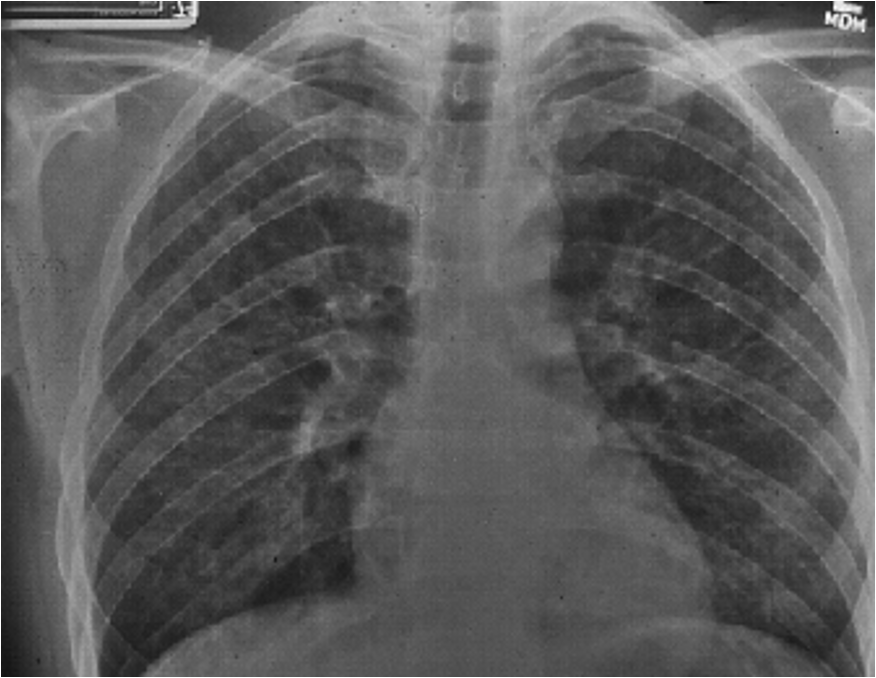

what would imaging studies show w/ PJP?

CXR: diffuse alveolar or interstitial infiltrates w/o effusions

CT: central ground glass opacifications in a perihilar distribution; spares periphery; septal thickening present; thin walled cysts